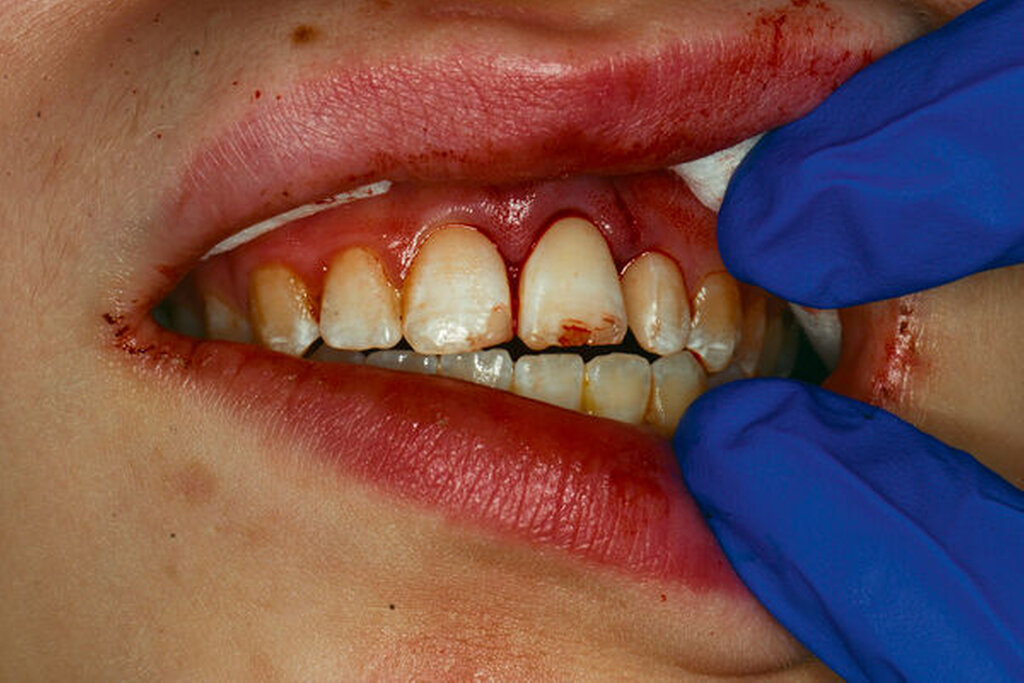

Bei einem dentalen Trauma kann es zu schweren Dislokationen der Zähne kommen. Zu den Dislokationsverletzungen gehören die Intrusion, die laterale Dislokation und die Avulsion des kompletten Zahnes als die schwerste Form der Dislokation. Bei diesen dislozierenden Zahntraumata kann von einer Verletzung oder Schädigung des Desmodonts ausgegangen werden – hier sind vor allem die Intrusion und die Avulsion der Zähne zu nennen (Abbildungen 4 und 5). In diesen Fällen wird ab dem achten Lebensjahr eine systemische Gabe von Doxycyclin zur antiresorptiven Therapie empfohlen. Die Datenlage zum klinischen Vorgehen der Antibiotikagabe ist bisher nicht eindeutig. Die Gabe des Doxycyclins beginnt am Tag des Unfalls mit einer Initialdosis von 100 mg für Patienten mit einem Körpergewicht von über 50 kg. Die Erhaltungsdosis beträgt für die kommenden sechs Tage zweimal täglich 50 mg. Kinder ab acht Jahre, die weniger als 50 kg wiegen, bekommen das Doxycyclin in einer Dosierung von 2 mg/kg Körpergewicht. Durch die kurze Gabe des Doxycylins sind Zahnverfärbungen sehr unwahrscheinlich. Des Weiteren hat bei über acht Jahre alten Patienten die Mineralisierung der Zahnkronen der ersten und zweiten Molaren bereits stattgefunden [Krastl et al., 2020] (Tabelle 2).

Ist der traumatisierte Zahn mit abgeschlossenem Wurzelwachstum um mehr als 1 mm aus der Alveole ausgelenkt worden, muss von einem apikalen Abriss des Gefäß-Nerven-Strangs ausgegangen werden. Die Regeneration der Pulpa bei einem ausdifferenzierten Foramen apicale (kleiner als zwei Millimeter im Durchmesser) ist extrem unwahrscheinlich, so dass es in diesen Fällen zu einer Pulpanekrose kommt. Über die Dentintubuli erfolgt nachfolgend bei traumatisierten Zähnen mit nekrotischer Pulpa eine bakterielle Kontamination – auch wenn die Zahnkrone intakt ist. Der Therapieentschluss über die Durchführung einer Wurzelkanalbehandlung sollte daher direkt am Unfalltag gefällt werden [Krastl et al., 2020] (Abbildungen 6 bis 9).